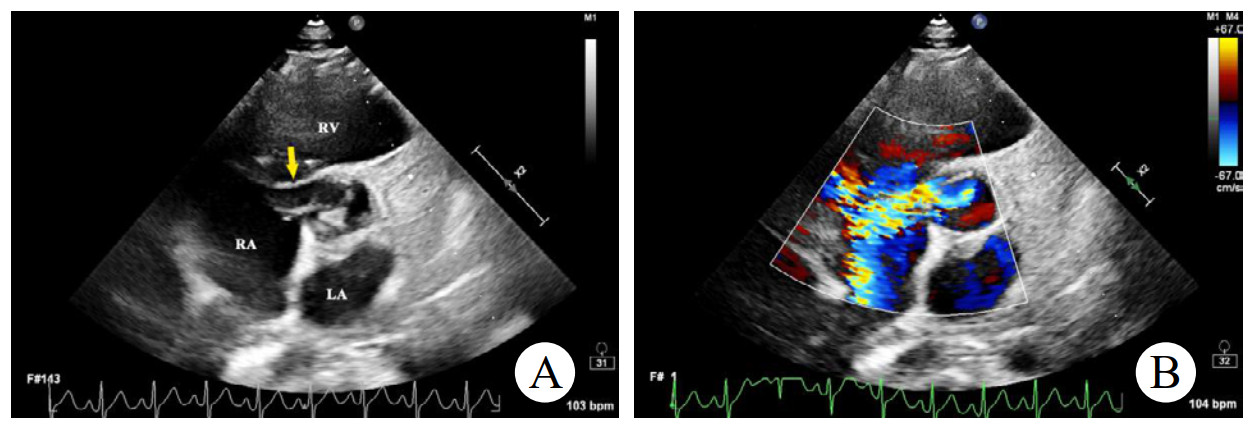

辅助检查如下。实验室检查:高敏C反应蛋白(hs-CRP)和红细胞沉降率(erythrocyte sedimentation rate, ESR)轻度升高。心电图:正常窦性心律,无ST段异常改变。胸部CT:双侧肺门中心对称分布的斑片状高密度影,部分实变,伴空气支气管征,病变边缘模糊。超声心动图:二维超声(2D)主动脉短轴切面显示右乏氏窦瘤破裂(ruptured of ASV, RASV),破入右心房形成“囊袋状”结构,长约1.7 cm,基底部破口内径约0.8 cm(图 1A)。彩色多普勒(color Doppler flow imaging, CDFI)显示全心动周期的左向右分流(图 1B)。连续多普勒(continuous doppler, CW)测得连续分流。室间隔内见4.0 cm×0.7 cm无回声区(图 2A),CDFI显示彩色血流信号随心动周期进出该无回声区(图 2B),考虑室间隔夹层瘤(dissecting aneurysm of the interventricular septum, DAIS)。实时双平面成像同步显示窦瘤破口与室间隔夹层相延续。应用Philips TrueVue三维(three-dimensional, 3D)超声心动图成像模式直观展示室间隔夹层瘤的立体结构(图 3)。

| 注:A为2D超声显示右乏氏窦瘤破裂(黄色箭头)突向右心房形成“囊袋状”结构;B为CDFI显示窦瘤破裂处自主动脉至右心房的左向右分流束 图 1 2D、CDFI显示主动脉短轴切面右乏氏窦瘤破裂情况 |